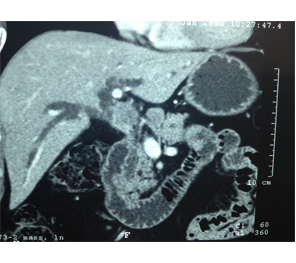

Large HCC in seg 2 & 3

CT Scan showing Lipoidol uptake in segment VIII